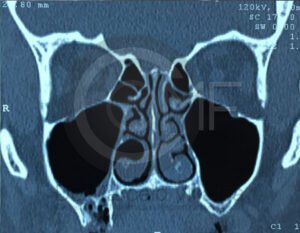

Es una conexión entre la cavidad oral y el seno maxilar que puede ocurrir tras extracciones o infecciones. Su tratamiento busca cerrar adecuadamente la comunicación para evitar molestias e infecciones sinusales.

El tratamiento depende del origen y gravedad de la infección. Puede incluir medicamentos, drenaje quirúrgico o procedimientos específicos para eliminar el foco infeccioso y evitar complicaciones.

En casos de mayor complicación deberá ser ingresado a cuidados hospitalarios, y programar el procedimiento quirúrgico que corresponda